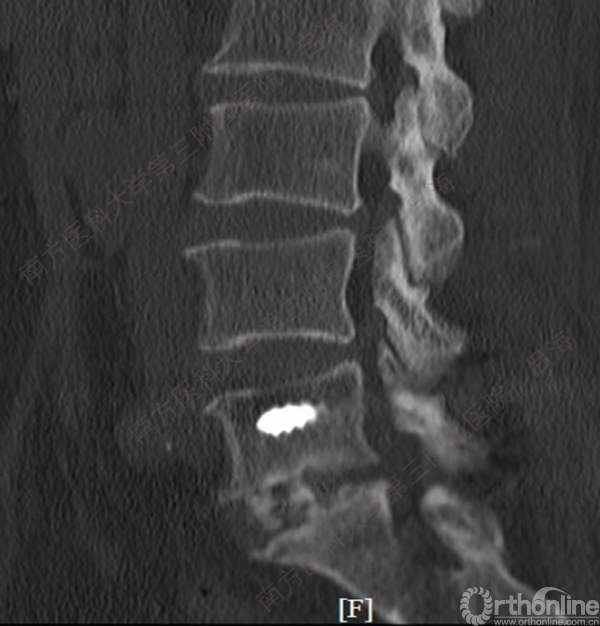

随着社会老龄化进程加快,胸腰椎退行性病变的治疗已经成为脊柱学术界的一个热点话题。MIS-TLIF手术可以治疗多种不同的胸腰椎退行性疾病,南方医科大学第三附属医院吕海教授结合病例为我们一一展示了该术式在治疗不同胸腰椎疾病时的具体手术过程。